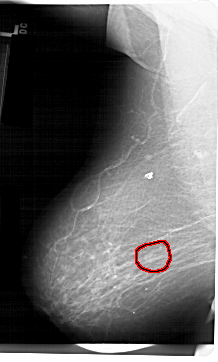

Digital Database for Screening Mammography

Volume: benign_03 Case: A-1366-1

A_1366_1.LEFT_MLO

FILE: A_1366_1.LEFT_MLO.OVERLAY

TOTAL_ABNORMALITIES 1

ABNORMALITY 1

LESION_TYPE MASS SHAPE OVAL MARGINS ILL_DEFINED

ASSESSMENT 4

SUBTLETY 4

PATHOLOGY BENIGN

TOTAL_OUTLINES 1

BOUNDARY